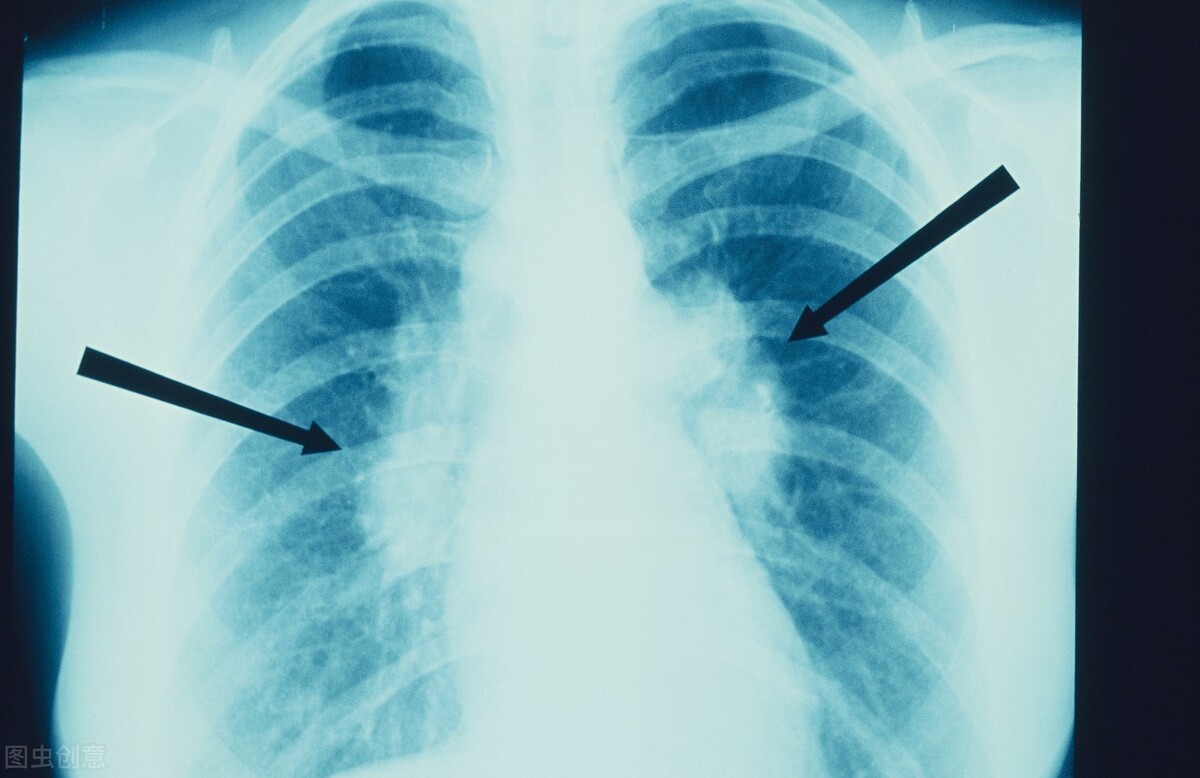

目前,医院采用影像学对肺癌进行初步判断,常用的是胸部CT检测。但想要确诊肺癌,最好是病理活检,也就是从患者肺部病灶内取出一块组织进行病理化验,这也是诊断肺癌的金标准。

肺结节是在肺部CT中直径小于3cm的类圆形或者不规则形状病灶。肺结节≠肺癌,CT筛查中仅有小部分肺结节存在恶性肿瘤的可能性。